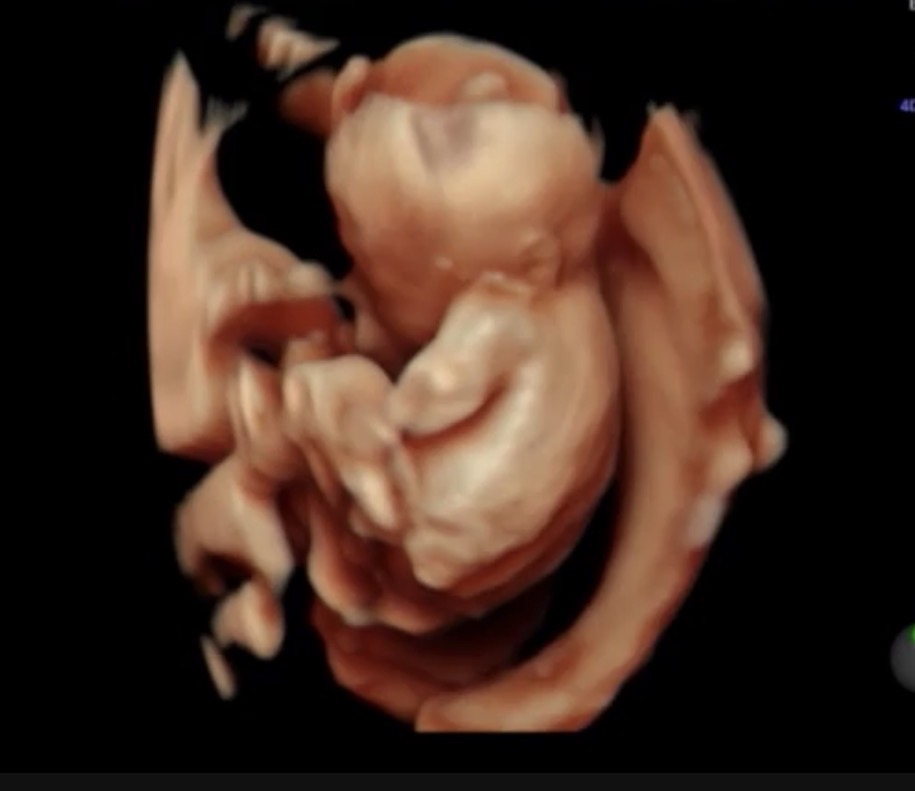

⑤30w0d|R先生から正式に女児確定

どうしても「確定」という言葉が欲しくて、30w0dの動画を送りました。

すると、ついに「女児完全確定」とのお返事をいただきました。

↑完全に女の子のシンボルが写っています。

ここでやっと、「本当に女の子なんだ」と実感することができました。

産み分けのゴールにたどり着いたような気持ちになりました。